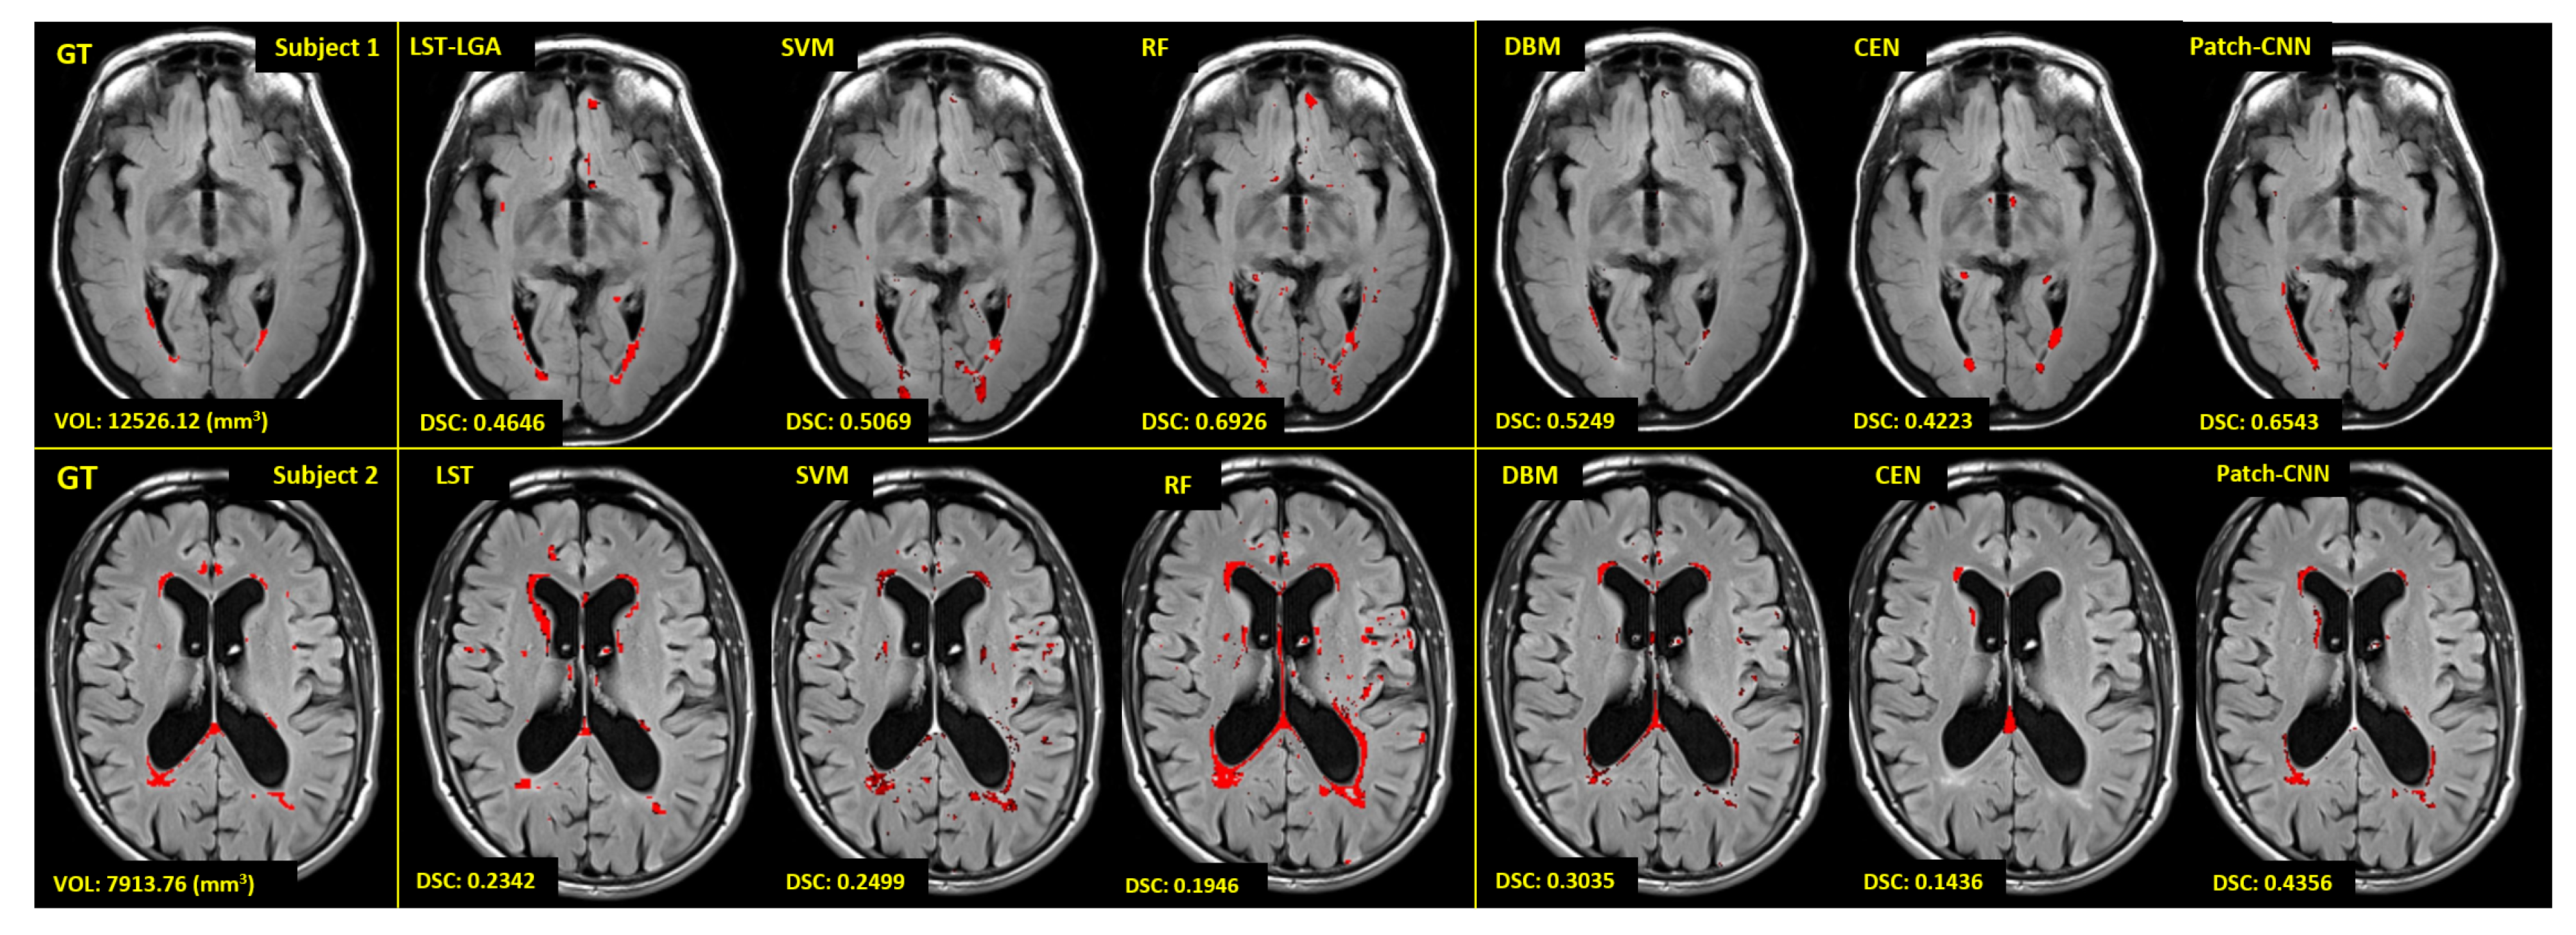

Some visual examples of WMH segmentation can be seen in Figure 9 where visualisations of ground truth (GT), LST-LGA, SVM-SET3, RF-SET1, DBM, CEN and patch-CNN are shown. Red regions in the figure are WMH segmented either manually (i.e., in GT) or automatically (i.e., by either conventional or deep learning algorithm). Please note that red regions in the figure are produced using the optimum threshold value for the probabilistic output from each respective learning algorithm listed in Table 4. Thus, visualisation in Figure 9 is the best expectation of WMH segmentation result for each learning algorithm. From the visualisation and its respected DSC value shown in Figure 9, deep learning produced better WMH segmentation results than the conventional ones. Furthermore, patch-CNN produced better WMH segmentation results than other deep learning algorithms.

Figure 9.

Visualisation of automatic WMH segmentation results from LST-LGA, SVM-SET3, RF-SET1, DBM, CEN and patch-CNN. Red regions are WMH labelled by experts (GT) or conventional/deep learning algorithms. We visualise two different subjects with very different WMH burden to see how the WMH volume affects the performance of conventional/deep learning algorithms. Volume of WMH and value of the DSC metric for each algorithm are at the bottom left on each respective image.